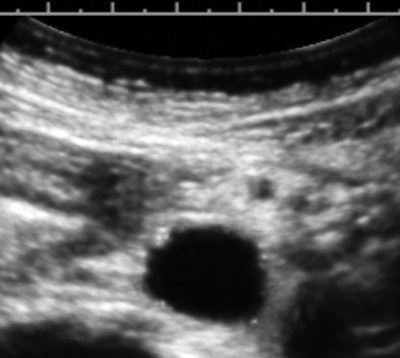

Here's a routine practice example that demonstrates the value of a medically centered exam technique. The image below is from the exam of an overtly healthy 47-year-old woman referred for heavy menstrual flow.

The image is a transverse cross-section of the distal abdominal aorta about 2 cm above the bifurcation. There are subintimal calcifications and a small plaque, which are distinctly pathologic, but now fairly common "incidental" findings at this woman's age.

In this case, a small extension to the exam resulted in confirmation of an abnormal lipid profile and the initiation of aspirin and statins. By being informed of the finding, the patient has motivation for the behavioral changes that will presumably have a major impact on her life span. As for the bleeding, that was a simple polyp.